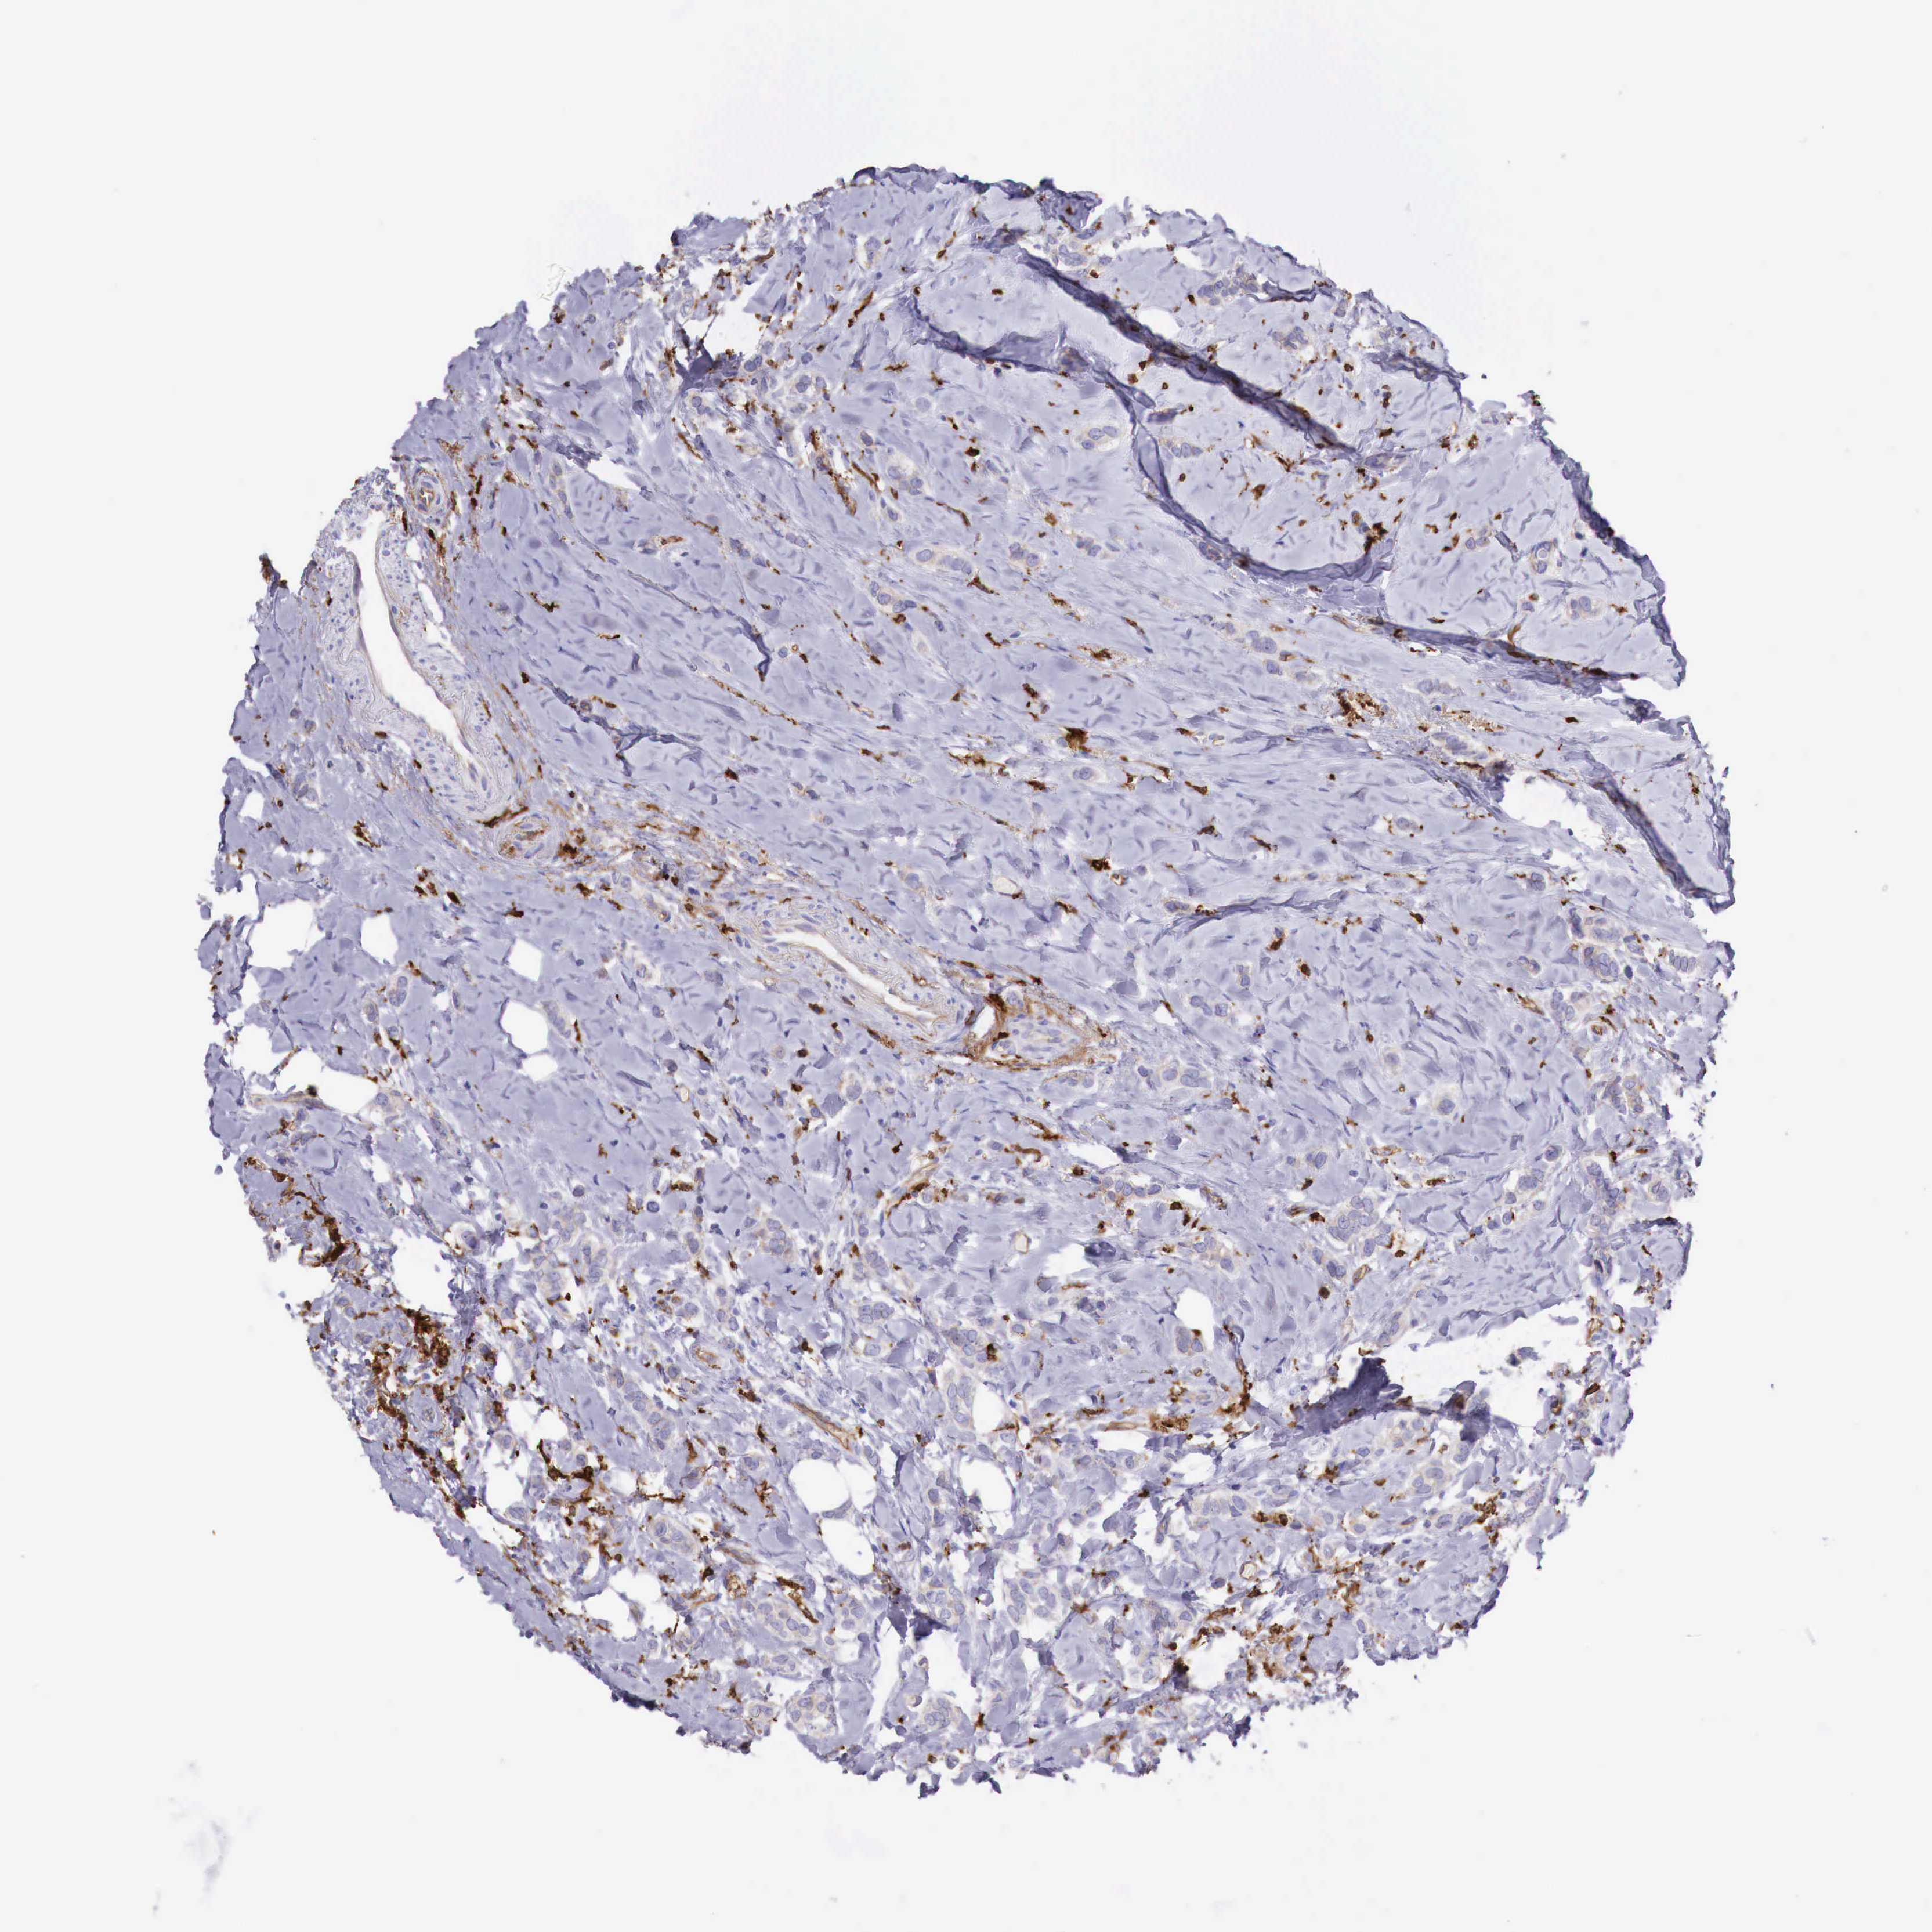

CANCER BREAST CANCER Show tissue menu

BRCA TCGA BRCA VALIDATION PROTEIN EXPRESSION